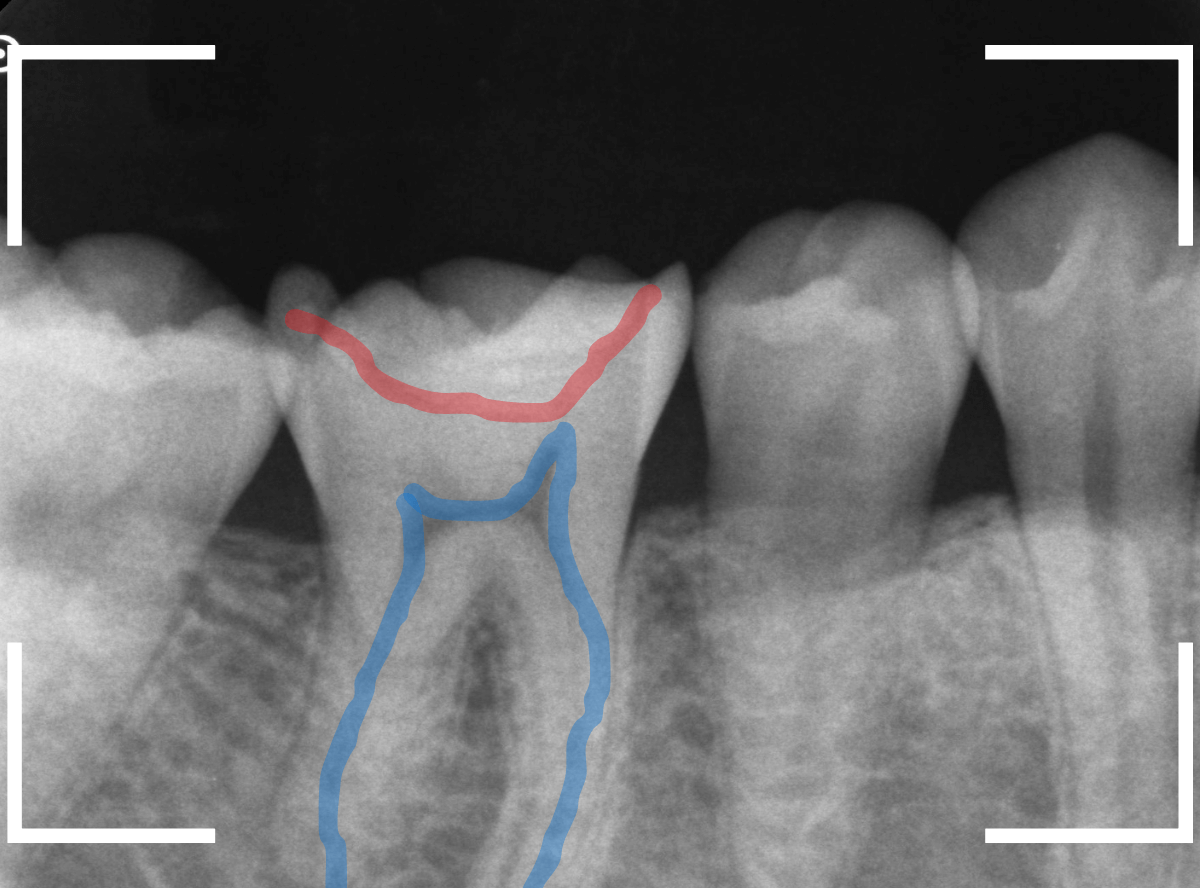

レントゲン写真で確認します。

赤い線がレジンが入っている部分。

青い線が歯の神経です。

かなり神経の近いところまでレジンがつめてあるのがわかりますが、虫歯が側面からどの程度進んでいるのかはよくわかりません。

レントゲン写真だけみると、治療の必要がなさそうにも見えます。

このように、初見では虫歯になっている事が明らかなのに、レントゲン写真ではまったくわからないとう事もあります。